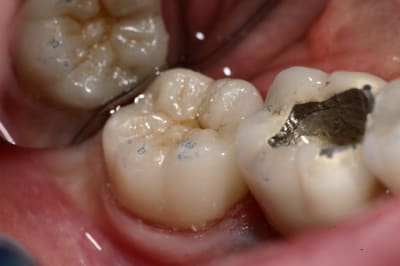

> Je ne vois pas quand un onlay n'est pas indiqué ?

> Même quand il ne reste rien, la preuve ci-dessous.

@ Steph : Sur un délabrement tel que celui de la photo présentée, on peut envisager que la tendreté de l'onlay composite amortit et absorbe les forces et préserve ce qu'il reste de cette molaire alors que ce ne sera pas le cas avec l'onlay céramique.

L'onlay répartit mieux les forces occlusales, et quand il s'agit d'onlay la céramique est recommandée.

Ici c'est de l'e-max.